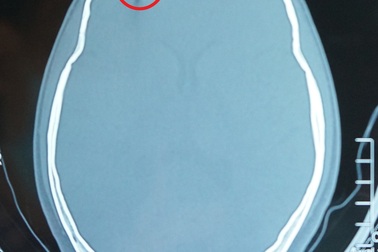

Nam thanh niên bị súng bắn đinh xuyên hộp sọSơ ý trong quá trình lao động, nam thanh niên bị chiếc đinh từ súng bắn xuyên hộp sọ phải nhập viện cấp cứu. Tai nạn lao động có thể cướp đi sinh mạng nạn nhân, cộng đồng cần chủ động phòng tránh.